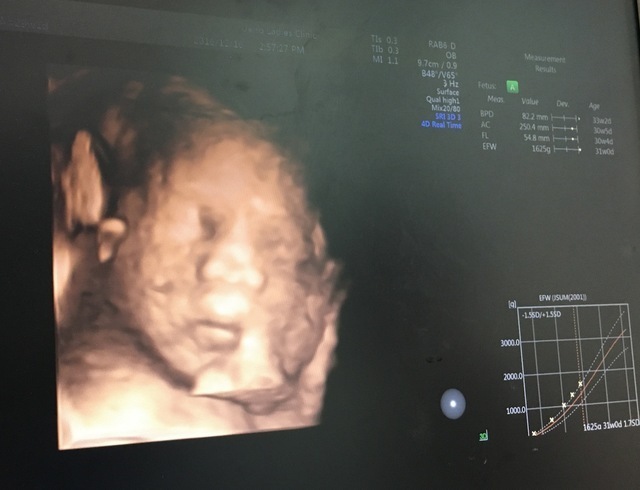

31週0日(31w0d・男の子)|京吾くんママ さん(21歳)

エコー写真撮影時のエピソード:

いつもエコーの時は顔を腕で隠していた息子ですが、初めて顔を見せてくれました。パパにそっくりで笑っちゃいましたが、この子がお腹の中にいるんだと思ったら余計に愛おしくなりました。産まれてからも寝顔はこのままです。(笑)